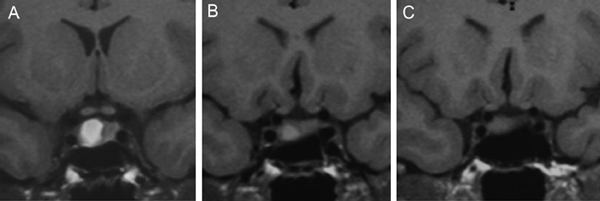

Figura 1A y B. TAC con contraste yodado, corte coronal, muestra un microadenoma lateralizado a izquierda (punta de flecha). Control a los 2 años. TAC con contraste yodado, corte coronal, demuestra aumento de volumen del microadenoma, lo que es infrecuente de observar en clínica (punta de flecha).

En los microadenomas el crecimiento tumoral es observado en una minoría de los casos (Figuras 1A y 1B), en contraste con los macroadenomas, los cuales cuando son encontrados en forma accidental (incidentalomas pituitarios) han demostrado un aumento de tamaño que varía entre 25 a 50%27-31.